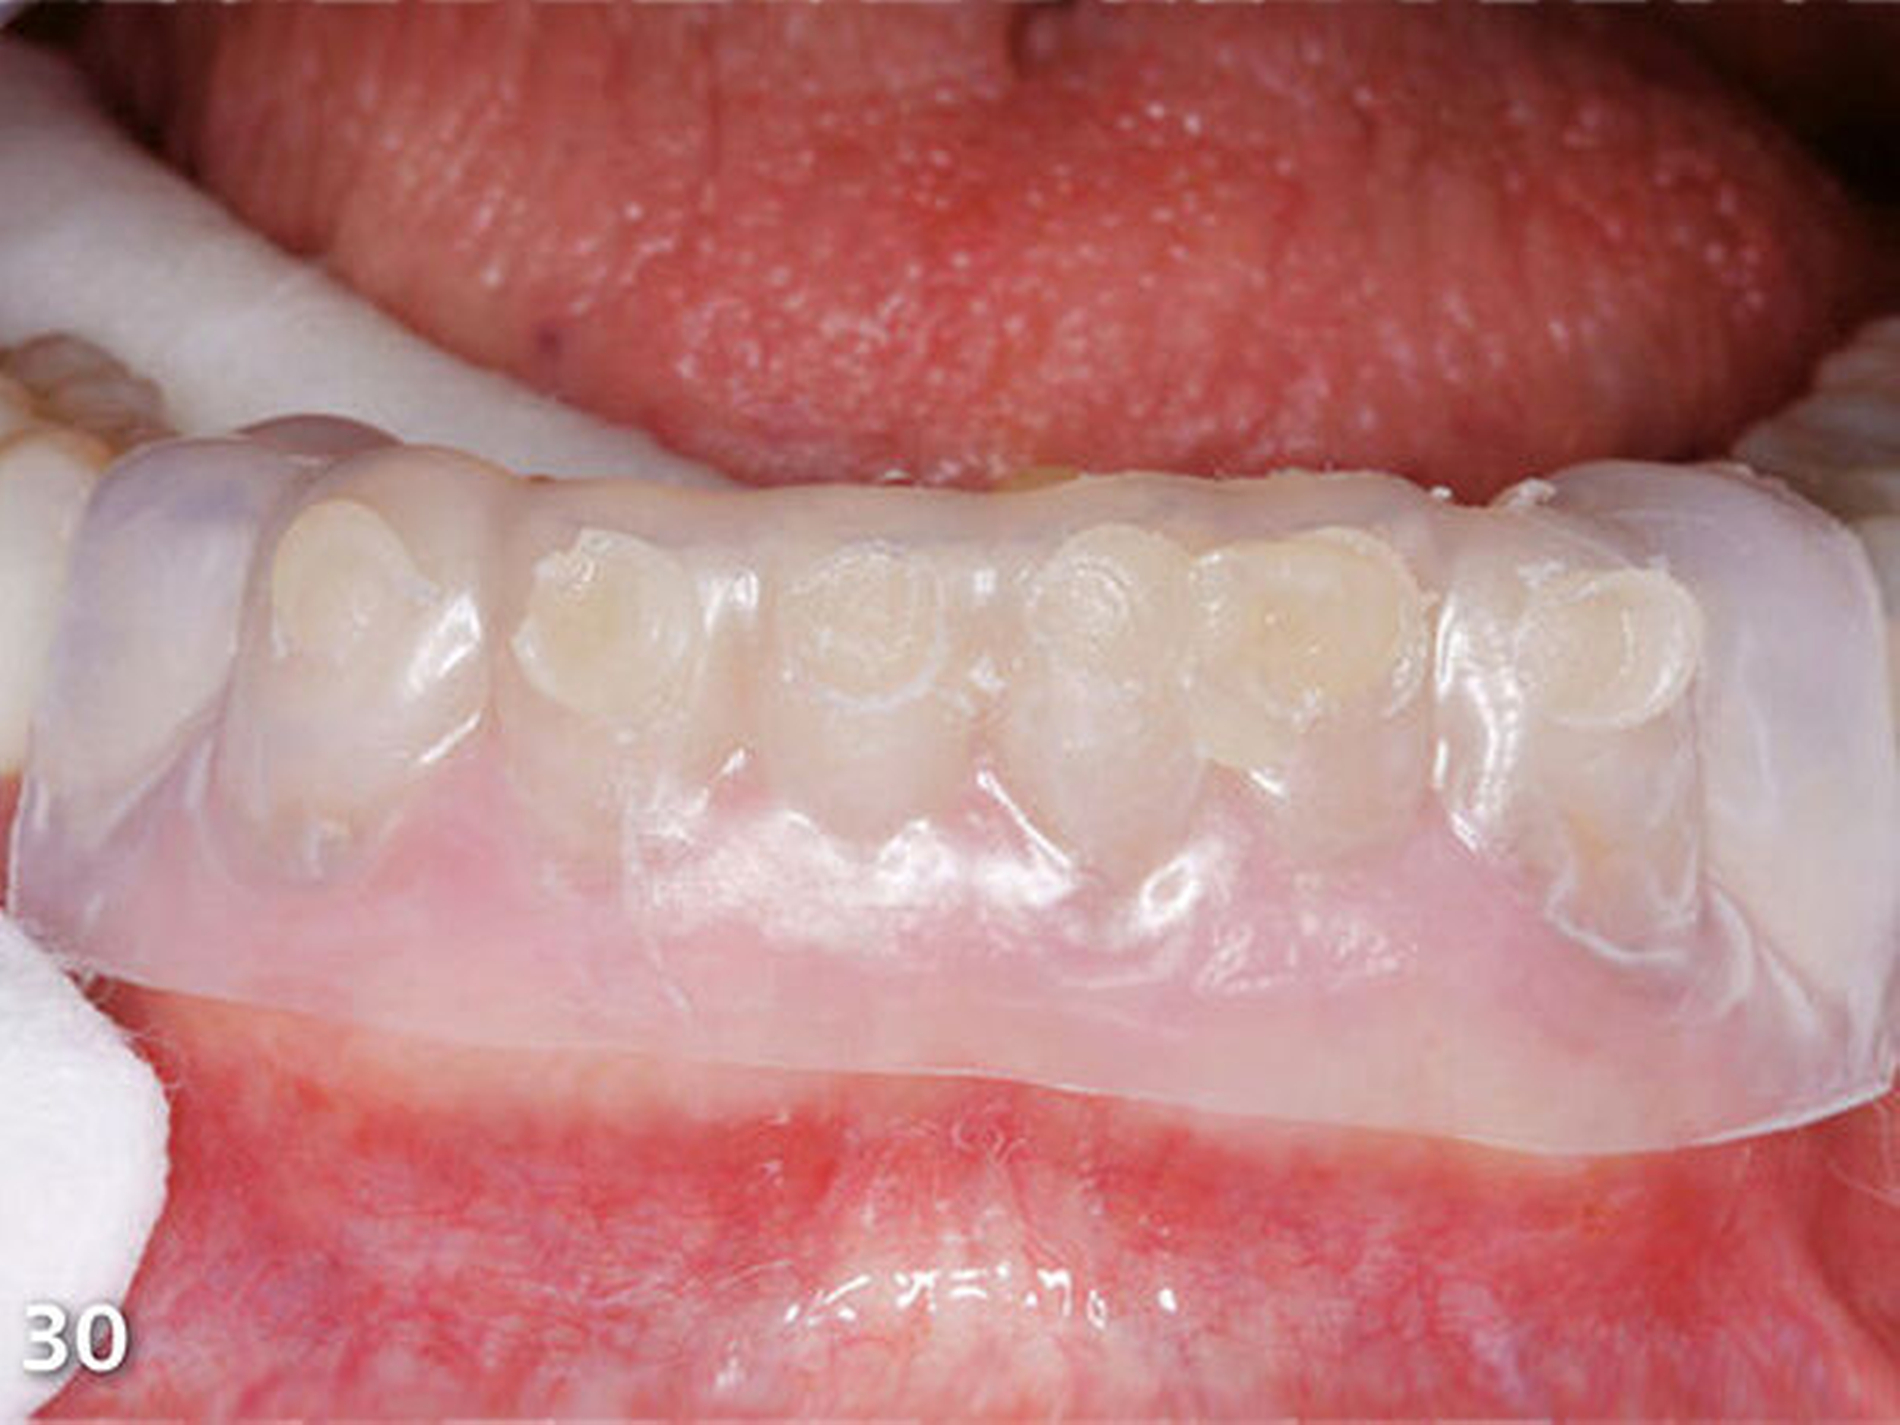

Analog erfolgte der Aufbau der Seitenzahnkauflächen der anderen Kieferhälfte ebenfalls in zwei Schritten (Abb.27). Durch den Aufbau aller Seitenzähne des Unterkiefers ist die temporäre Bisshebung bereits weitgehend abgeschlossen (Abb.28). Mit der dritten Übertragungsschiene (Schiene 3) (Abb.29) wurden die Unterkieferfrontzähne nach Ätzung der Zahnhartsubstanzen mit Phosphorsäure und nachfolgender adhäsiver Vorbehandlung inzisal aufgebaut (Abb.30).